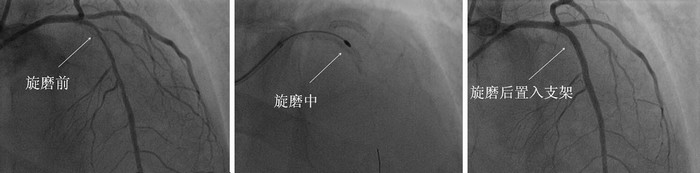

近日,我院CCU收治了一名58岁男性患者黄先生,他有长期吸烟史和高血压病、糖尿病病史。因反复胸痛25小时住院,入院后诊断为急性下壁心肌梗死,行冠脉造影检查提示回旋支为心梗“罪犯血管”,开通梗死相关冠脉,左前降支仍存在80%弥漫狭窄,行前降支球囊扩张时发现病变严重钙化,球囊扩张失败。经与患者家属沟通病情,决定择期实施冠脉内旋磨术,清除左前降支内钙化斑块后,再植入支架。心内科CCU介入团队在安贞医院心内科专家指导下,经过术前积极充分的准备后开始了手术。穿刺右桡动脉为手术通路,指引导管连接冠状动脉,旋磨头焊接在一根长而柔软的螺旋旋转导管上,经导管进入冠脉钙化处,由其后接的气轮机驱动高速旋转,其转速为140000-160000转/分钟。先后用直径1.25mm、1.5mm、1.75mm旋磨头旋磨20余次,终于铲除了这些血管里的“石头”,并成功植入支架。术后患者恢复良好,即日便可出院。

冠状动脉旋磨术采用高速转动的带有微型钻石颗粒的旋磨头将钙化、纤维化的斑块磨碎成为<12um大小的微粒,可进入血液循环并由吞噬细胞清除,使冠状动脉内膜光滑度增加,管腔扩大,顺应性增加,为下一步支架置入“打开通路”。冠状动脉斑块旋磨术的成功率90%~95%,尤其是严重钙化病变的介入治疗成功率明显提高。因此对于一些球囊可能无法通过或病变难以扩张开的严重狭窄伴重度钙化病变,冠状动脉旋磨术可以降低血管内膜撕裂发生率、降低支架脱载发生率以及支架膨胀不全导致的支架内血栓形成。